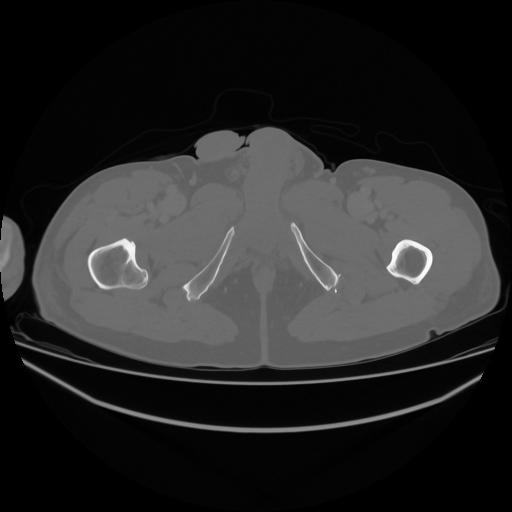

5 CUERPO,CE,Vol,1.0,CUERPO,,